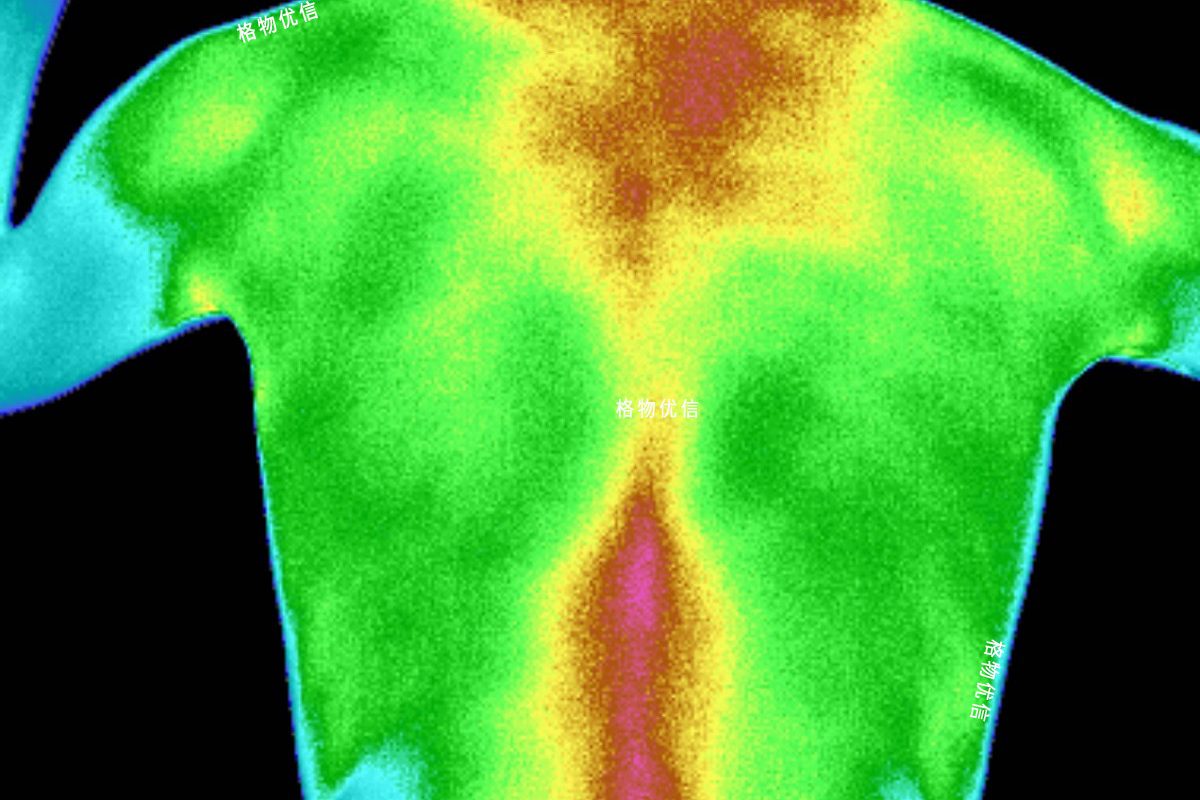

紅外在醫(yī)學(xué)上的應(yīng)用

1800年英國科學(xué)家赫胥爾在一次物理實驗中偶然間發(fā)現(xiàn)了紅外輻射,人類開始研究這種不可見光,到20世紀(jì)初,普朗克…